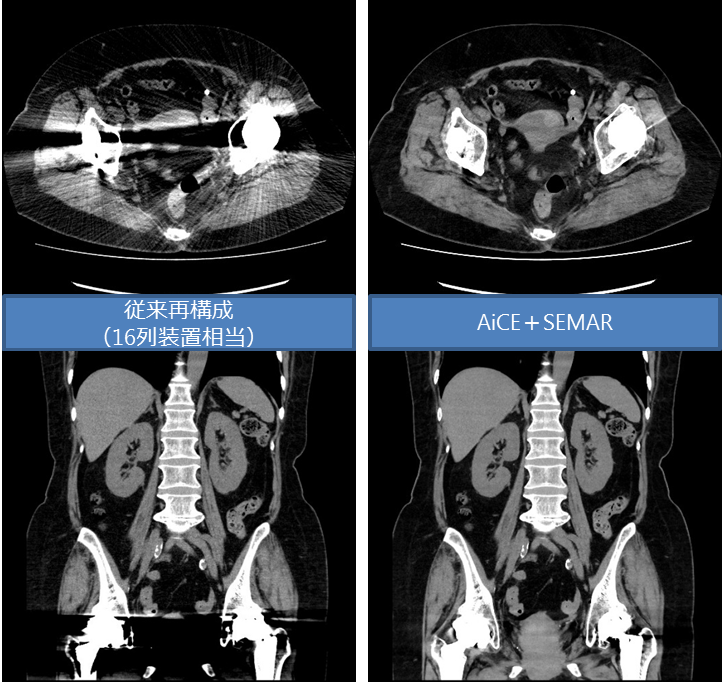

さらに、新しく体内金属からの画像劣化を最小限に抑える技術(SEMAR)も搭載しており、股関節など金属置換後の患者様にも高画質の検査が可能となりました。

<股関節金属置換後>